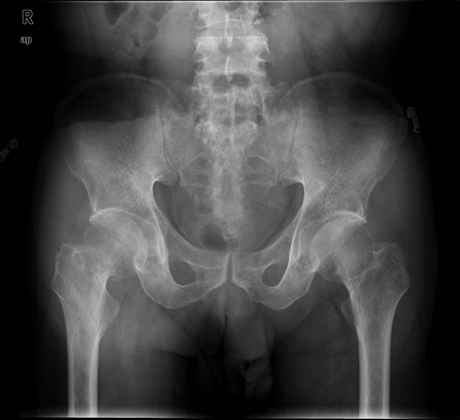

영상 진단: X-ray, CT 스캔, 또는 MRI를 통해 골절의 정확한 위치와 심각성을 파악합니다.